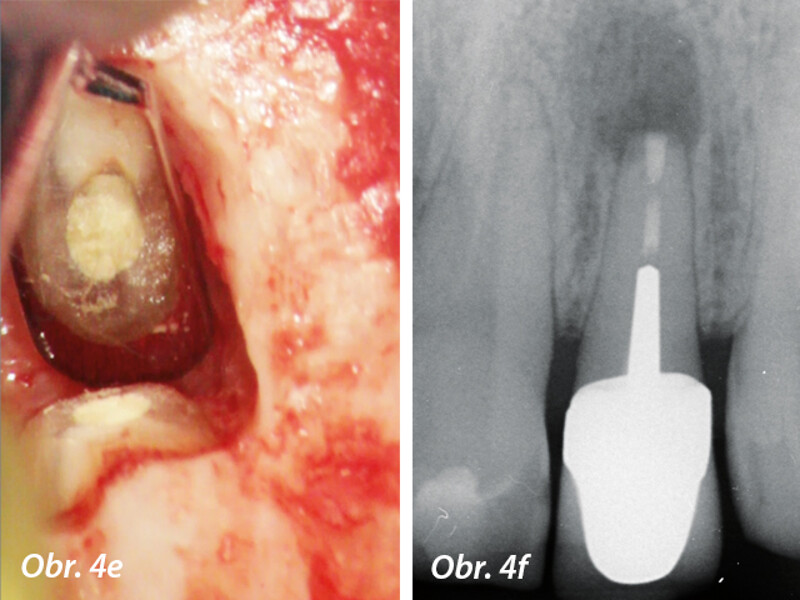

Aplikace MTA s použitím Produit Dentaires (PD) MAP System